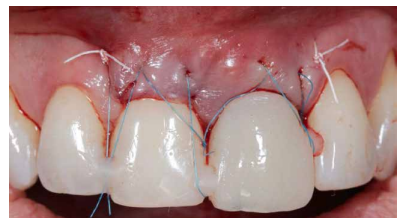

Los beneficios de la carga inmediata incluyen una reducción notable de las intervenciones quirúrgicas, una menor dilatación temporal del tratamiento e incluso un mejor bienestar psicológico y social para el paciente. En casos con importante compromiso estético, la carga inmediata o la provisionalización inmediata, añadida a la colocación inmediata postextracción del IOI permiten minimizar las alteraciones derivadas de la pérdida dental, manteniendo el perfil de emergencia, contorno de tejidos blandos y las papilas gingivales5-7.

Así mismo, se han establecido diferentes protocolos para el manejo del sector estético anterosuperior, que se suman al acto de la colocación inmediata del implante y la corona provisional, donde se incluyen la colocación de un material no reabsorbible entre el IOI y la cortical vestibular para minimizar el posible colapso, así como el manejo de los tejidos blandos periimplantarios8-11.